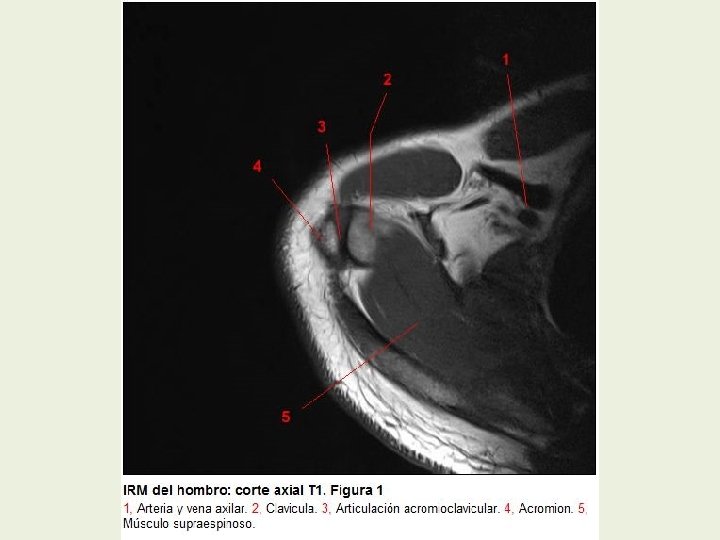

Hombro Cortes axiales RMN